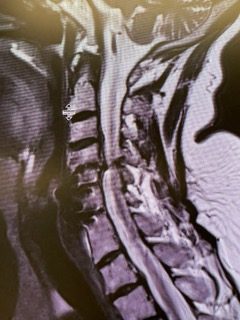

Spine:

Central Cord Syndrome

Author: Yusef Imani M.D., F.A.A.N.S., Read More!

Cervical Laminectomy and Fusion

Author: William Sonstein M.D., F.A.C.S., Read More!